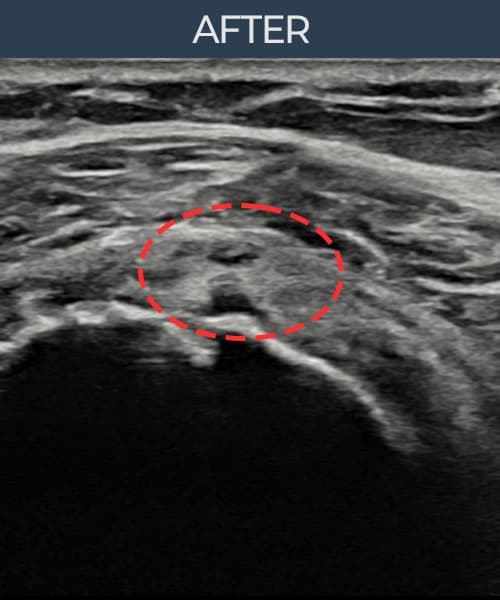

超声确认旋转肌腱袖 部分撕裂(6mm × 3mm (肌腱厚度约35%缺损))。缩小缝合术后肌腱连续性恢复,患者回归正常生活。

术后

术前超声确认旋转肌腱袖 部分撕裂,冈上肌腱回声不连续伴肌腱缺损(6mm × 3mm (肌腱厚度约35%缺损))。术后超声显示撕裂部位充满再生组织,肌腱连续性恢复,回声模式正常化。

该患者持续肩痛。详细超声检查确认旋转肌腱袖 部分撕裂(缺损:6mm × 3mm (肌腱厚度约35%缺损))。在超声引导下实施非手术缩小缝合术。术后佩戴支具约4-6周,随后进行分阶段康复锻炼。随访超声确认肌腱连续性恢复、结构稳定,患者顺利回归日常生活。